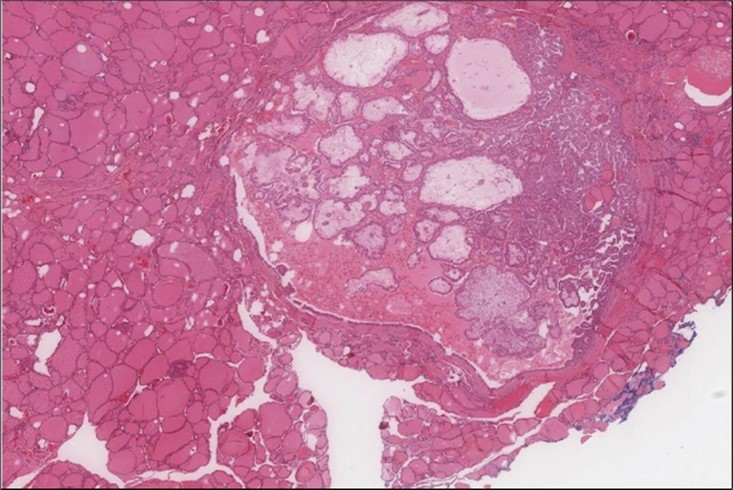

Figure 5.Liver biopsy Lower power of the liver core showing normal liver and part of the metastatic foci (H&E, x4)

cancer, or other metastatic tumors without further testing with genetic or molecular studies 3, 7. Immunohistochemical testing plays a vital role in differentiating LMS from such similar tumors as it stains positive for vimentin and smooth muscle actin (SMA), and is variably positive for HHF35, desmin (50%-100%), and H-caldesmon 3, 6. Moreover, there were no reported cases where thyroid LMS stained positive for thyroglobulin, cytokeratin, calcitonin, chromogranin, or protein S100 3. Our patient’s left thyroid biopsy showed the characteristic microscopic features and was positive for SMA, desmin, caldesmon, P63 with patchy EMA (Figure 1, Figure 2, Figure 3, Figure 4) as well as her liver biopsy (Figure 5, Figure 6, Figure 7); whereas her right thyroid showed clear papillary thyroid cancer cell features (Figure 8, Figure 9).